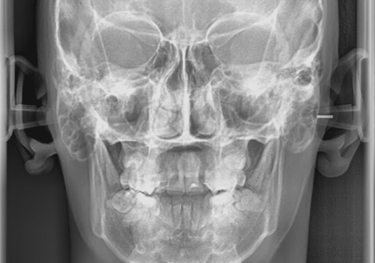

TELERRADIOGRAFIA FRONTAL